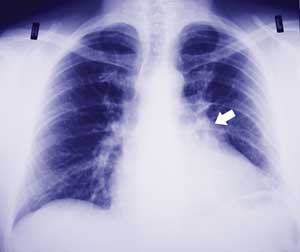

A 41-year-old man was referred for open biopsy of a 3 cm left lung lesion. The lesion had been discovered incidentally on chest x-ray (Box, A) and investigated with a computed tomography scan of the chest (Box, B) and a fine needle aspiration biopsy under radiological guidance that was inconclusive.

A: Chest x-ray showing the incidental finding of a left hilar mass (arrow).